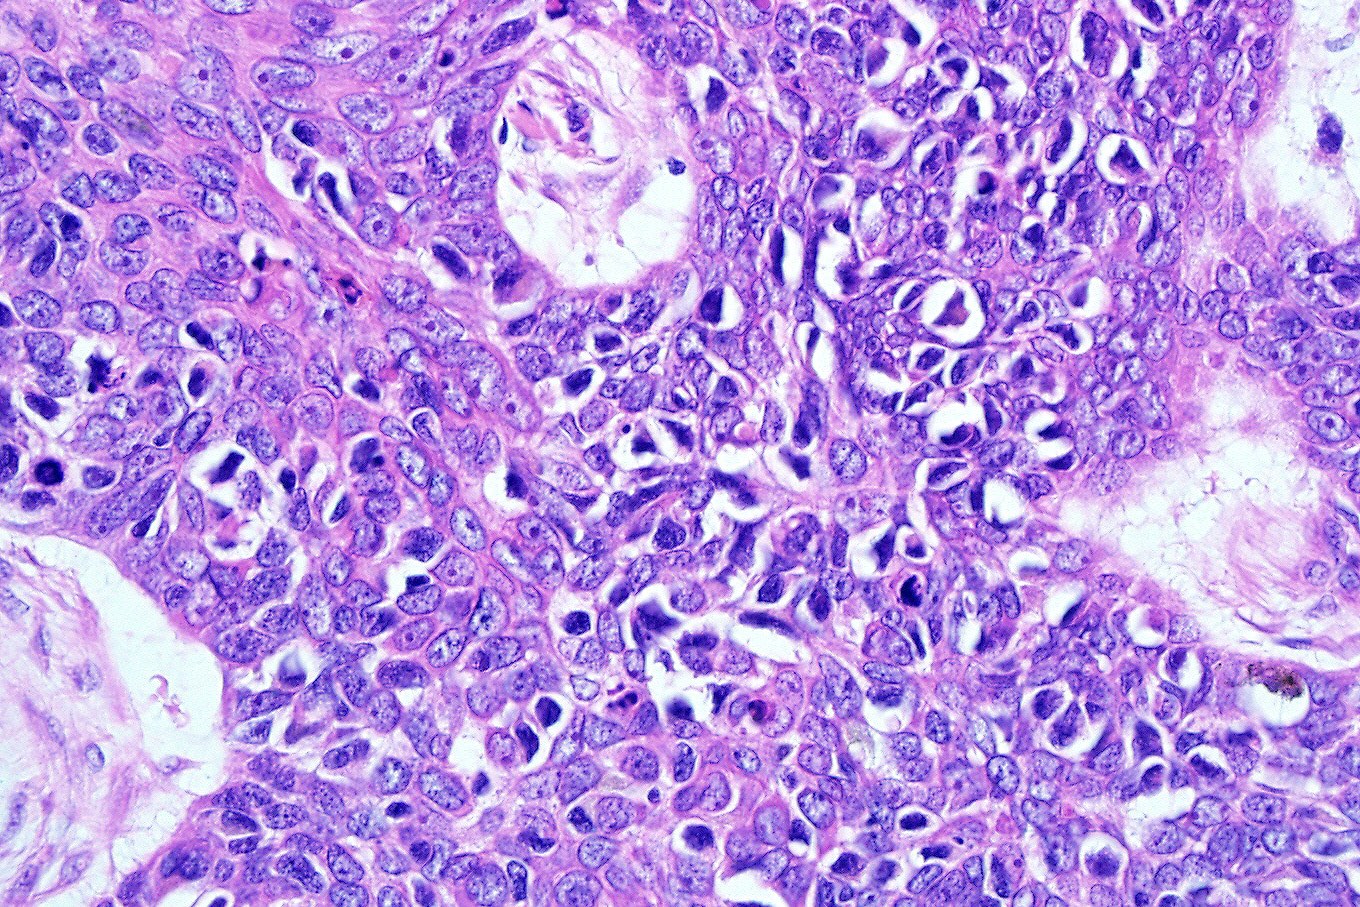

- Basosquamous (metatypical) BCC

- Biphasic tumor

- Foci of neoplastic squamous differentiation

- Pleomorphic (giant cell, BCC with monster cells) BCC

- Mitotic activity

- Apoptosis

- Сellular pleomorphism and giant cell formation

- Atypia has no prognostic significance

Microscopic (histologic) images

Contributed by Antonina Kalmykova, M.D., Phillip H. McKee, M.D., Sate Hamza, M.D., Eduardo Calonje, M.D.,

Wayne Grayson, M.B.Ch.B., Ph.D., James Sampson, M.B.B.S., M.Sc. and Assia Bassarova, M.D., Ph.D.